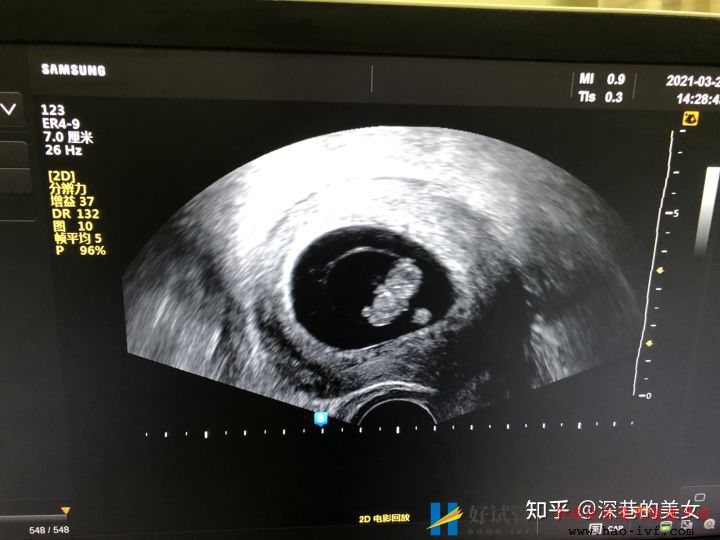

多囊卵巢的促排经历(已怀孕)_好试管网